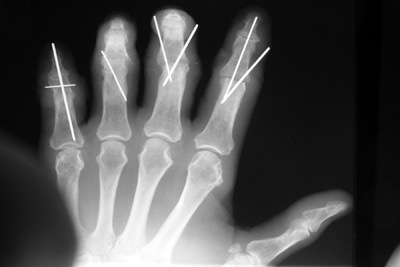

Although it was known to be high risk, JJ felt his life would be over without the use of his hands for woodworking, and insisted upon finding a team who could take on this challenge. Dr. Badia and Dr. Khouri would later successfully reattach all four fingers after the patient was flown by helicopter to Cedars Medical Center. We can see that JJ not only regained enough use of his hand to tie his shoes and perform gardening, but he also completed the task he began when he met his accident.